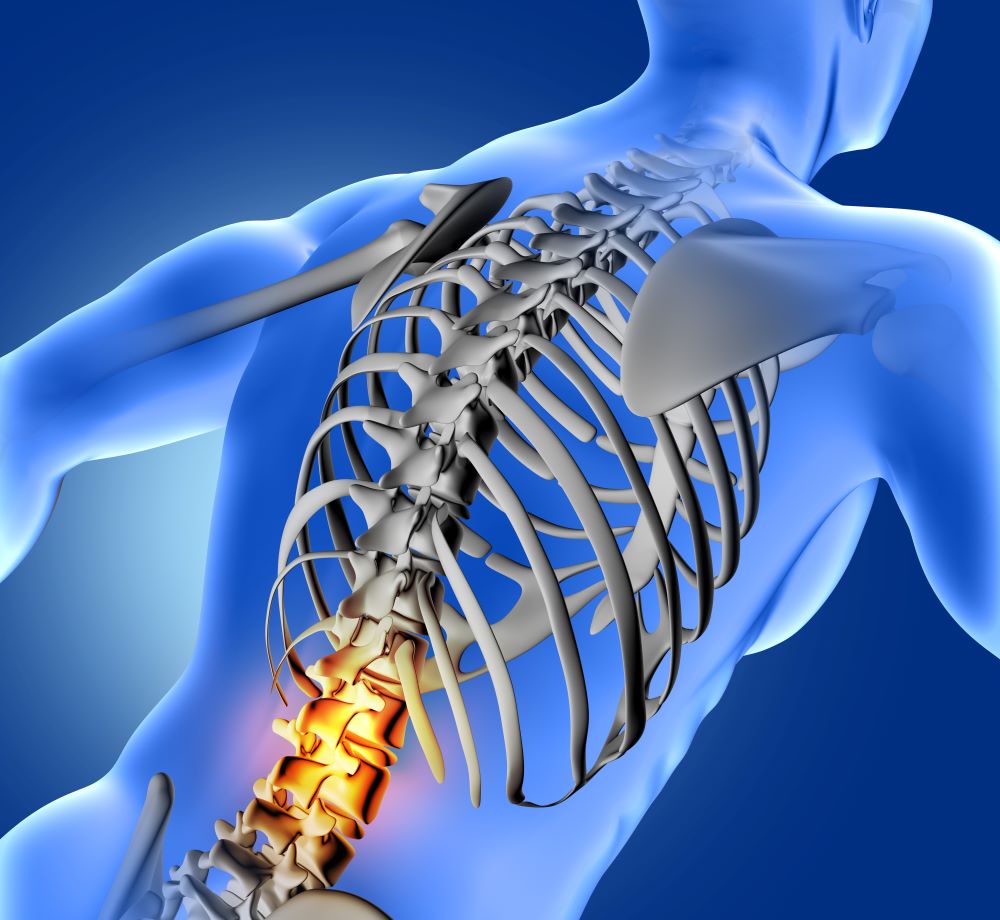

Физичката активност е најдобрата превентива за да се избегнат деформитетите кај децата, но мора да се прават и редовни контроли и да се следат децата во нивниот раст, со цел навремено да се реагира, вели дипломираниот кинезитерапевт Јован Каланоски.

Не секогаш какви и терапевти да сме, можеме да го решиме проблемот со деформитетите кај децата. Најважно е навремено откривање и почнување со преземање мерки, дали е тоа спорт, корективни вежби, корсети за корекции, истегнувања….Навремената реакција е многу битна. Затоа им им велам на родителите да си ги гледаат децата, еднаш месечно да ги проверуваат, ако видат некоја асиметрија кај рбетот да се консултираат со стручни лица. Имаме три раста кај децата и ризикот во тие е голем за појава на деформитети. Не знаеме во кој правец ќе тргне рбетот, дали правилно или во друга насока и тогаш треба да се прати, вели Каланоски.

Корекција на вроден деформитет преку мануелна терапија е бесмислено. Пршлените се така вродени и нивната структура е многу различна во споредба со нормалниот. Кај вродените деформитети треба да се внимава да не прогресираат или минимално да прогресираат. За жал, имаме и задоцнети случаи. Сколиозата е најопасен тродимензионален деформитет кај децата, искривени се во три димeнзии, прогресира страшно многу во тие три растови. Детето не расте во висина, се криви на една страна, на друга страна. Ако тука навреме не се реагира и процентот на деформитет премине некоја критична точка многу е тешко да се корегира до безбеден степен, додава Каланоски.

Причините за сколиозите, вели, не е дефинирана, ако не е вродена, а девет спрема еден е соодносот на застапеност кај девојчињата во споредба со момчињата, што можеби е и резултат на поголемата физичка активност на момчињата, за разлика од девојчињата.

`Рбетот е е една моќна конструкција и со мал деформитет можеме да живееме, но да биде во нормални граници. Многу ми е мило што во училиштата има наставници по физичко образование уште од прво одделение зошто тие го следат балансот или дисбалансот на телото кај детето. Потребна е многу почеста комуникација со родителите, но и да се прават систематски прегледи на три-четири месеци кај стручни лица. Мора свеста да се подигне, мораме децата да ги следиме, заклучува Каланоски.